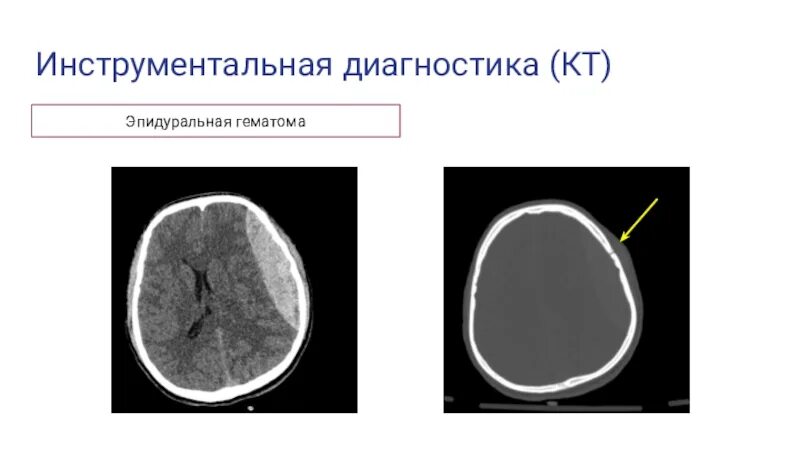

Объем гематомы на кт